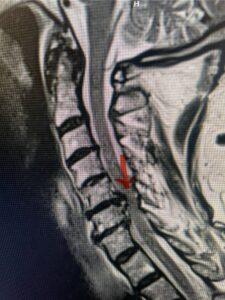

Fig. 7a Sagittal and axial T2-weighted cervical MRI’s demonstrating spinal cord compression slightly to the left secondary to disc/osteophyte complex (red arrow)

Fig. 7b